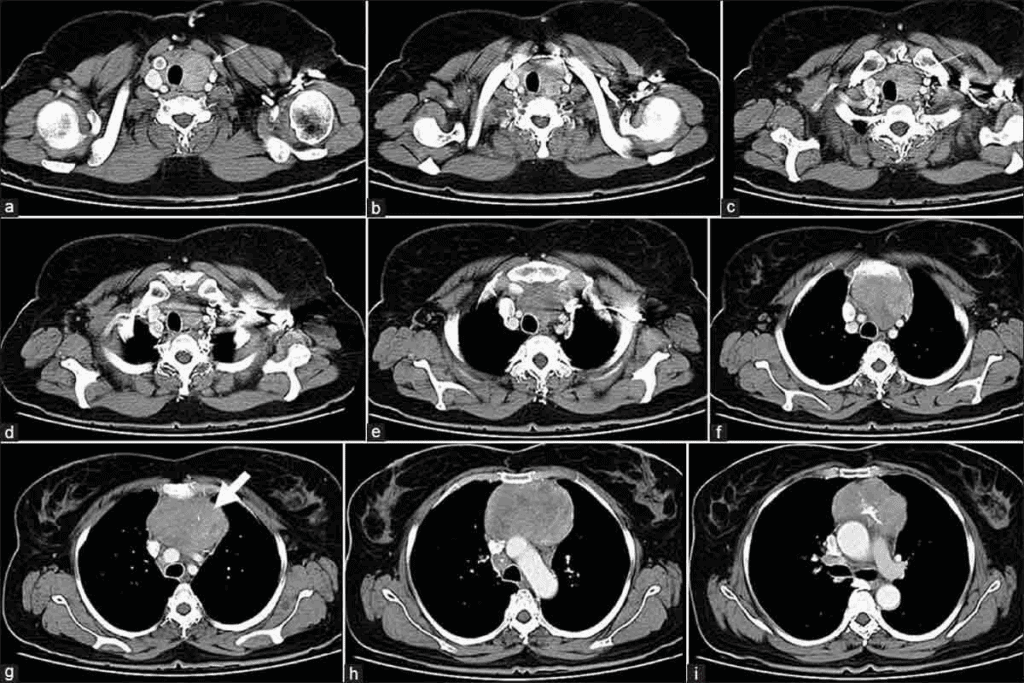

How CT Technology Creates Detailed Cross-sectional Images

Chest CT scans combine X-rays and computer tech for detailed images. An X-ray tube moves around the body, taking many pictures. These pictures are then put together into a 3D image.

This image shows the chest’s inside parts clearly. It includes soft tissues, blood vessels, and lungs.

It’s great at showing soft tissues and areas around the lungs and heart. This helps spot problems that X-rays can’t see.

Detailed Visualization Capabilities of Chest CT Scans

Chest CT scans give us a clear view of the chest area. This helps doctors make accurate diagnoses and plan treatments. Our team uses the latest CT technology to get high-quality images. These images help in managing different chest conditions.

Blood Vessel Imaging and Contrast Enhancement

When we add contrast to chest CT scans, we get a clear view of blood vessels. This is vital for spotting issues like pulmonary embolism and checking blood vessel health. Contrast agents make blood vessels stand out, helping us find any problems.

Heart and Surrounding Structures Assessment

Chest CT scans also show us the heart and nearby areas. We can see the pericardium, heart chambers, and coronary arteries. Our radiologists are skilled at looking at these areas for any issues.